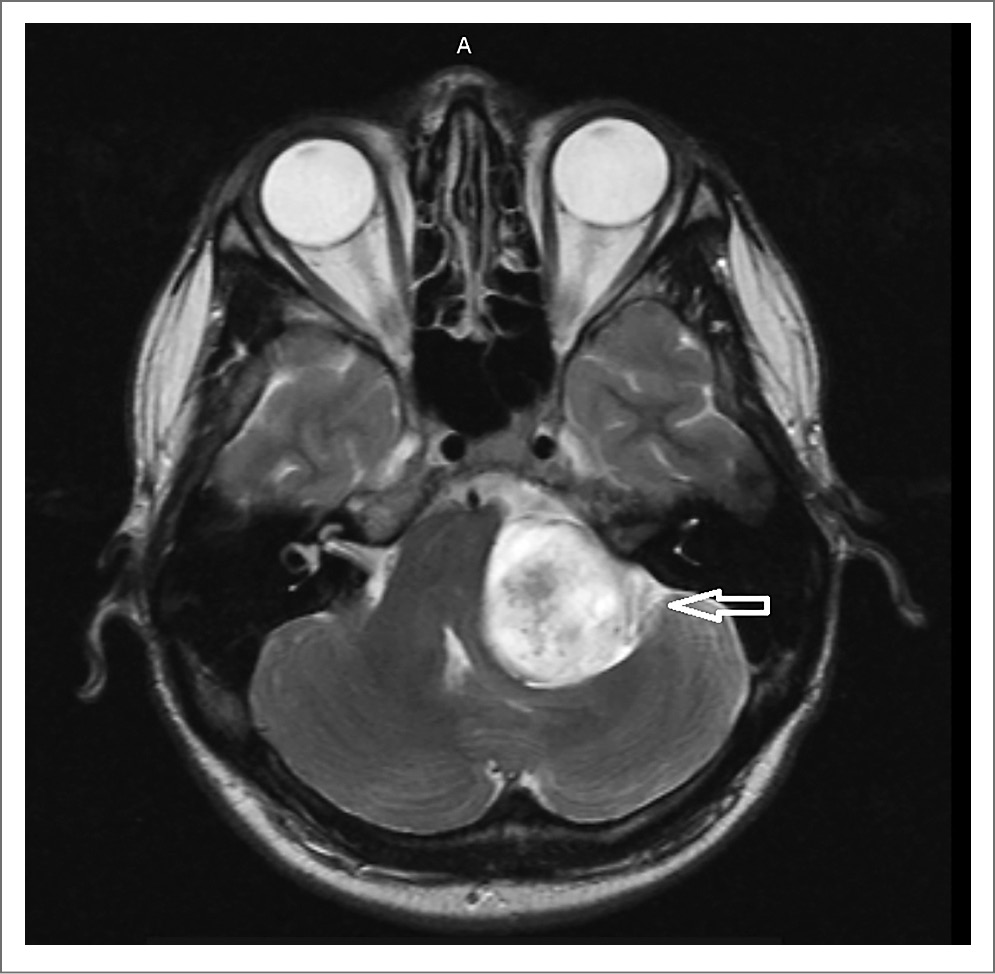

Пациент явился на повторный прием 15.12.21 с результатами магнитно-резонансной томографии (МРТ) головного мозга (рис. 1, 2). Заключение: «МР-картина объемного образования левой гемисферы мозжечка. Учитывая наличие сифилиса (со слов пациента) в анамнезе, МР-картина может соответствовать гуммозной форме нейросифилиса. МР-картина дислокационного синдрома продолговатого мозга, начальные признаки окклюзионной гидроцефалии. Единичные гиперинтенсивные очаги в белом веществе головного мозга, вероятно, как проявление микроангиопатии».

Рис. 1. Результаты МРТ головного мозга пациента И. (стрелкой отмечено объемное образование левой гемисферы мозжечка).

Пациент повторно проконсультирован неврологом. Диагноз: «нейросифилис с симптомами. Гуммозная? форма. Дислокационный синдром. Астенический синдром. Вестибуло-атактический синдром». С учетом изменений, обнаруженных на МРТ головного мозга от 11.12.21, пациенту необходима экстренная госпитализация в нейрохирургический стационар. От предложенной госпитализации по каналу скорой медицинской помощи пациент отказался, оформлен отказ от госпитализации в присутствии лечащего врача и заведующего МГРЦДС. Дано направление на госпитализацию. Пациенту разъяснены результаты дообследования и возможные осложнения.